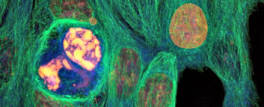

Nanotechnology Tool Offers a Better Prognosis for Brain Cancer

A new nano-fabricated platform for observing brain cancer cells provides a much more detailed look at how the cells migrate and a more accurate ...